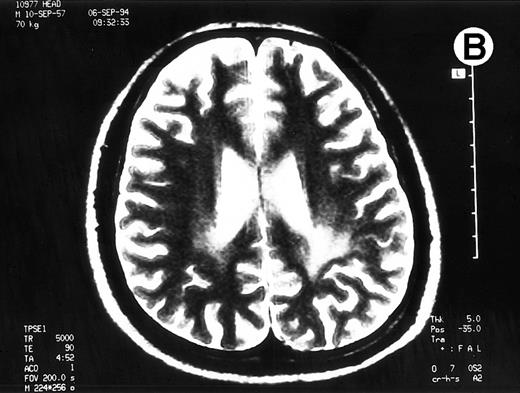

Paths of blight signal on T2-weighted MRI in white matter of brain adjacent bilateral posterior lateral ventricles. (A) On day 526 when we just withheld cyclosporine. (B) On day 698 when chronic GVHD resolved by readministration of cyclosporine.

To rule out the possibility of CsA neurotoxicity, although the trough levels of CsA ranged from 130 to 170 ng/mL, we withheld CsA at day 526. Despite this attempt, the CNS lesions on MRI did not change, and we subsequently restarted 150 mg/d of CsA at day 537. Thereafter, the CNS lesions gradually resolved with 150 mg/d of CsA and 10 to 20 mg/d of PSL (Fig 1B), coinsident with resolution on the other signs of cGVHD. The seizures never recurred with 600 mg/d of sodium valproate. The patient has now minor CNS lesion and mild signs of cGVHD with 100 mg/d of CsA and with 90% of Karnovsky score at 62 months following allo-BMT.